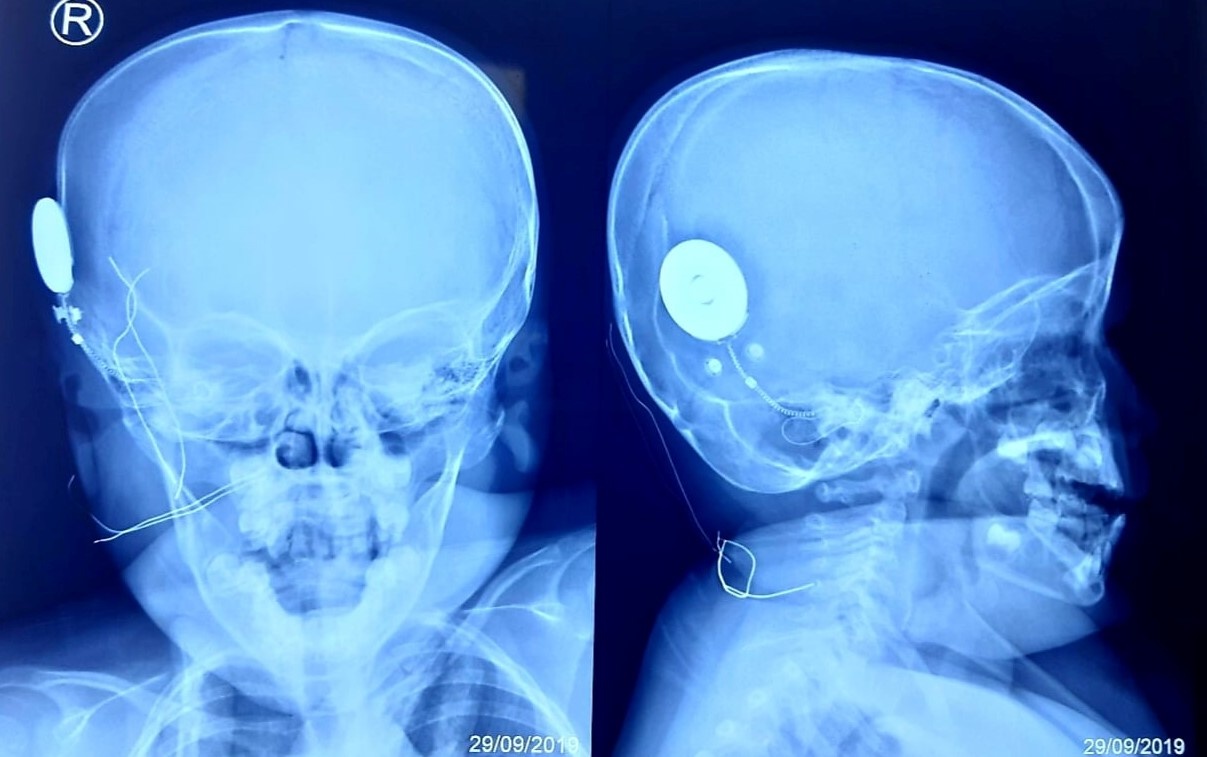

![]() |

| Hình ảnh chiếc tai điện tử sau khi được cấy vào ốc tai bệnh nhi. Ảnh: BVCC. |

Sau 2 giờ thực hiện phẫu thuật, các bác sĩ đã đặt điện cực vào trong ốc tai của bé. Các chỉ số hoạt động của điện cực (trở kháng, trường, đáp ứng thần kinh hạch xoắn) sau khi cấy đều cho kết quả tốt.